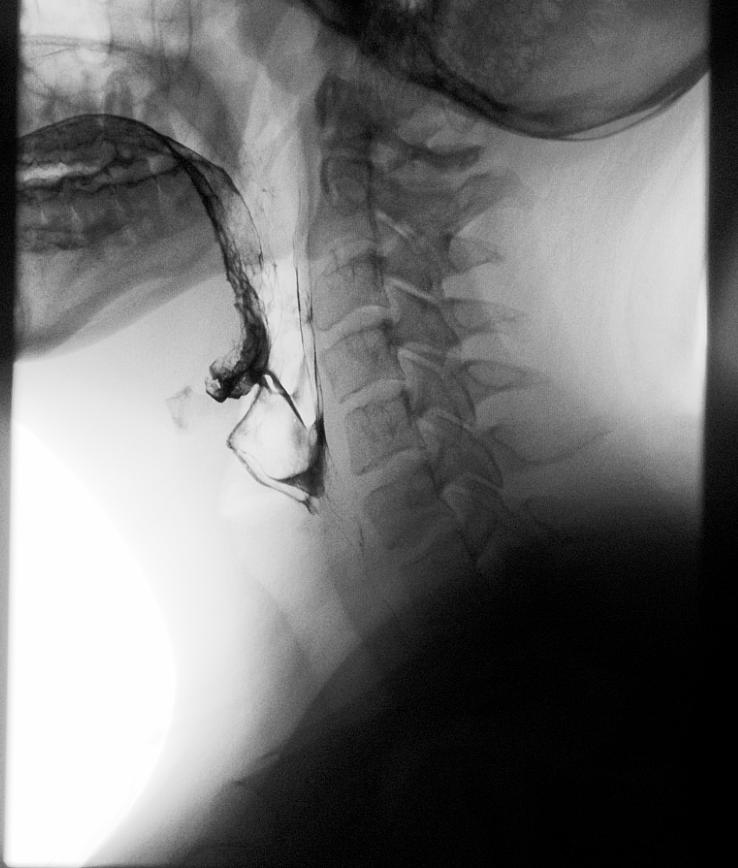

In terventional radiology (IR) departments diagnose and treat disease. IR professionals treat a wide range of conditions in the body by inserting various small devices, such as catheters or wires from outside the body. X-ray and imaging methods, such as CT and ultrasound help guide the radiologist. Interventional radiology can be used instead of surgery for many conditions. In some cases, it can eliminate the need for hospitalization.

few. Creating process improvement committees, task forces and multidisciplinary tumor boards provide a platform to showcase advanced techniques utilized in IR. A great example of collaborative care in IR would be a patient receiving treatment for neuro aneurysm coiling procedure then proceeding to OR for an aneurysm clipping procedure. Another example would be a patient with liver cancer receiving chemoembolization in the IR suite then systemic therapy from the oncologist. The multidisciplinary approach can decrease length of stay and provide better patient outcomes.

GE HealthCare’s Allia Platform represents the culmination of a multi-year collaboration with interventionalists and surgeons aimed at enhancing user experience, improving workflow efficiency, and increasing the adoption of advanced image guidance in daily practice. Designed to be a trusted assistant for image guided therapies – the Allia Platform features a robotic gantry with a smaller footprint than previous versions and other features to enhance user experience and improve workflow integration and efficiency. With just one click, users can access all of their essential functions to make it their own personalized workplace that meets the operator’s specific needs and

preferences in the interventional or hybrid operating room. Similarly, with the redesigned C-arm making the controls more accessible, it enables an optimized ergonomic setup for the user’s clinical needs, even in complex working positions at the head, neck or left side.

To further advance interventional innovation in image guided therapy, GE HealthCare also continues to expand its offerings of solutions that utilize digitization and artificial intelligence (AI) to help clinicians deliver precision care. The company’s ASSIST imaging software helps users easily access and use augmented reality to help precisely plan, guide and assess sophisticated interventional procedures with greater precision and dose efficiency. Embo ASSIST AI is the latest addition to the suite of ASSIST solution offerings designed to automatically segment vascular structures to facilitate embolization workflow planning, as well as help clinicians visualize and anticipate the destination of potential injections to support their embolization strategy thanks to AI-based simulation.

3The ARTIS icono ceiling, a ceiling-mounted angiography system from Siemens Healthineers, provides imaging guidance for a wide range of routine and advanced interventional radiology and cardiovascular procedures. Its design flexibility combines with intelligent workflows and advanced positioning accuracy. The system’s rotational capabilities and simplified C-arm cabling enable superfast cone beam computed tomography (CT) data acquisitions for reduced motion artifacts and less patient contrast dose. The new Xpand feature¹ enables transverse movement of the C-arm at the push of a button, permitting easier positioning for radial access and allowing the user to move the C-arm out of the way when direct patient care is required. Predefined Case

Flows permit precise intraoperative guidance and excellent clinical outcomes with minimal user interaction, faster system positioning, and low patient radiation dose. The new OPTIQ exposure control uses a contrast-based technique that is supported by intelligent, self-adjusting algorithms. OPTIQ automatically considers the source to image distance (SID), collimation settings, grid status, and patient thickness; it also determines and applies the optimal combination of the five available radiation exposure parameters and the detector dose as an additional variable. This exposure control is designed to achieve the requested contrast-to-noise ratio while prioritizing dose reduction.